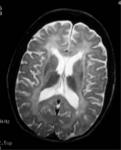

Metahromatska Leukodistrofija

Metahromatska leukodistrofija je oboljenje kod koga je deficijentnienzim aril sulfataza A. U beloj supstanci mozga i mijelinskim omotačimaperifernih nerava nagomilavaju se cerebrozid-sulfatidi. Do nakupljanjasulfolipida dolazi u jetri, bubrezima i drugim organima.